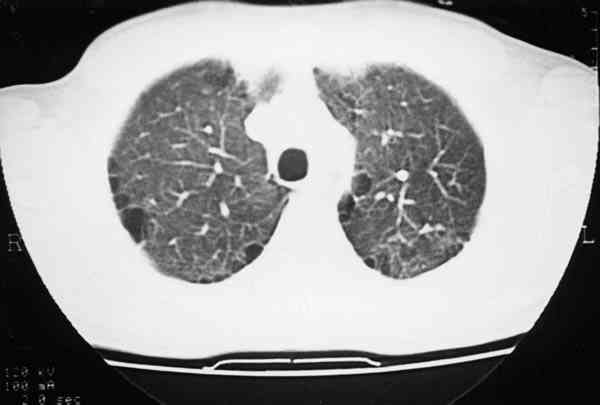

Figura 4

MÚLTIPLES IMÁGENES ENFISEMATOSAS BULLOSAS QUE HAN DESCRITO DE FORMA EXCEPCIONAL EN CASOS DE NEUROFIBROMATOSIS GENERALIZADA.